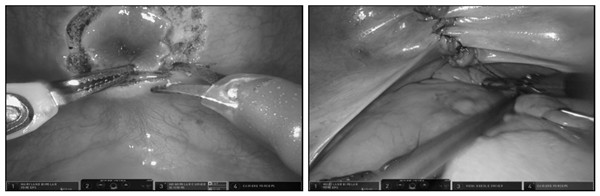

近日,泌尿外科种铁团队开展经膀胱途径机器人辅助腹腔镜下根治性前列腺切除术,据悉该术式为中国西部首例,具有开创性意义。

2021年11月15日及16日,在种铁教授的悉心指导下,泌尿外科李钊伦副主任医师、李建平主治医师医疗组、付德来副主任医师、唐骁爽主治医师医疗组先后完成2例经膀胱途径机器人辅助腹腔镜下根治性前列腺切除术。手术过程中麻醉科李芳团队和手术室董春丽和王嘉龙护理团队给予积极配合与支持,目前病人术后恢复均良好。

泌尿外科目前已经拥有6名取得机器人操作证书的医师。在种铁教授的带领下,机器人团队不断学习创新、攻坚克难,已经完成泌尿外科各种高难度机器人辅助手术近400余例。经膀胱途径机器人辅助腹腔镜下根治性前列腺切除术,可最大限度保留前列腺周围组织,包括尿控相关的盆底组织与结构和性功能相关的性神经。术后无需留置引流管,术后第1天即可下床。这一术式的开展为前列腺癌的手术治疗开启了一扇更加微创的新“大门”,将给前列腺癌接受手术治疗的患者带来更好的尿控和性功能保护效果。